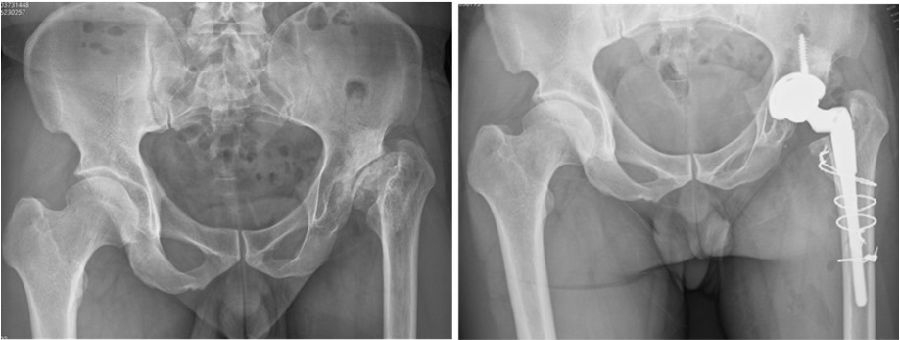

1、术前设计

随着医学技术及智慧骨科的发展,术前设计逐步实现从二维到三维再到机器人辅助技术的演变,为股骨近端畸形的治疗提供了新思路。

①术前CT,测量前倾角。

②双下肢全长X线,准确测量肢体不等长的程度。单侧DDH高脱位,看似狭窄、缩短,但绝对长度可能较对侧长。

③特殊假体的准备:小号假体、细直柄假体、组配假体、短柄假体,截骨准备:cable。

④机器人、AI-HIP能使术前计划更精准。